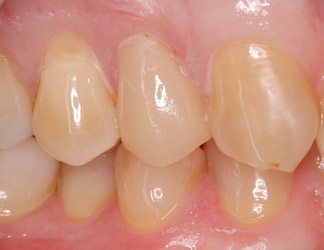

Cas 1 : 1 première prémolaire